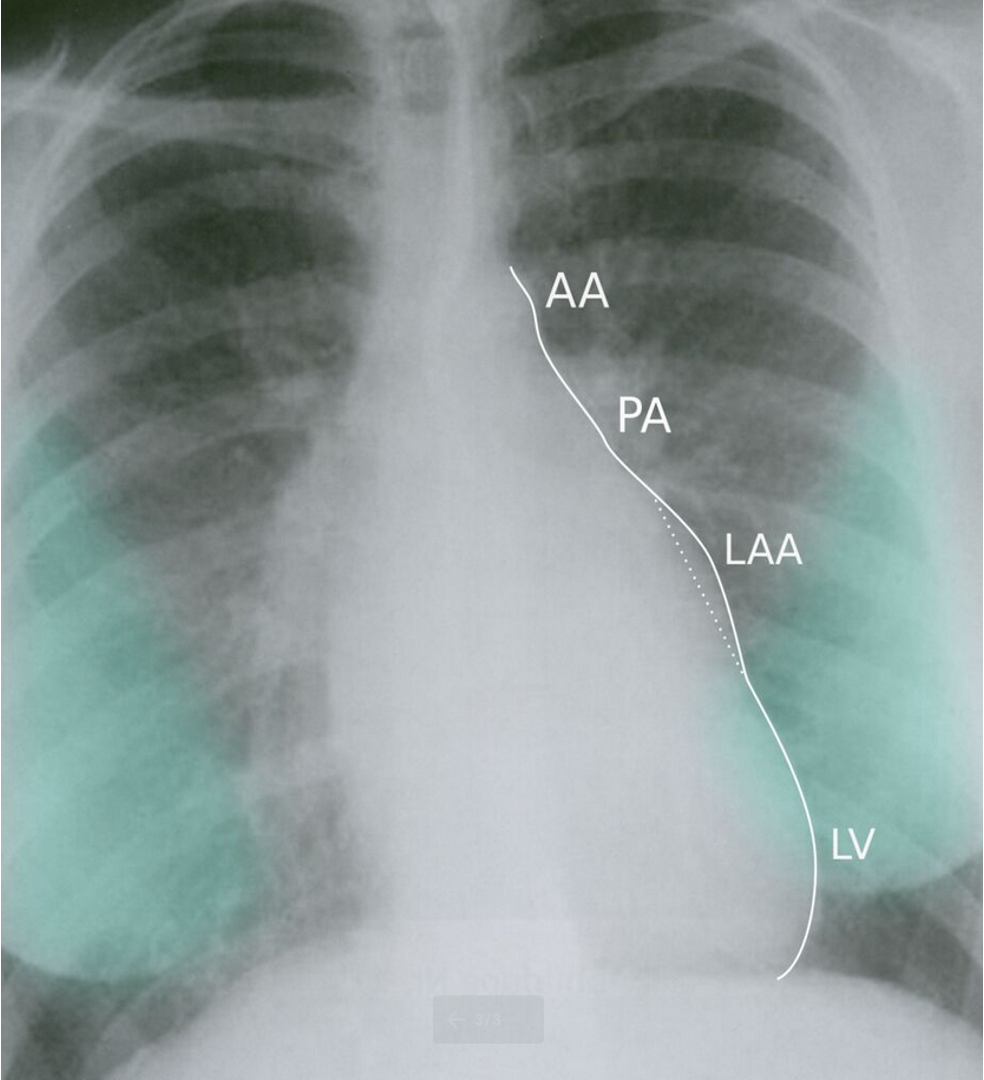

CXR Z

• Left atrial enlargement

• Mitralisation of heart: straightening of left heart border

• Elevation of left mainstem bronchus

• Evidence of mitral calcification

• Evidence of pulmonary edema kerley’s b lines

• Double contour of the right border of heart

Imaging

PA view: ⇒ Left atrial enlargement:

• Convexity or straightening of the left atrial appendage.

• Left heart border is straight or convex

• Double density of RT  cardiac border

• Elevation of the left main bronchus and splaying of the carina

LA view: posterior protrusion of the upper part of posterior heart border.